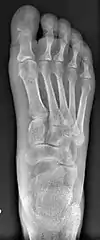

Fig. 8a. Painful hallux valgus and metatarsus primus varus deformity recurrence of left foot after osteotomy surgery

1. For recurrence correction after osteotomy procedure (Fig. 8)

Late deformity recurrence can happen after osteotomy (bone-breaking) procedures because osteotomy surgeries do not specifically stabilize first metatarsal bone.